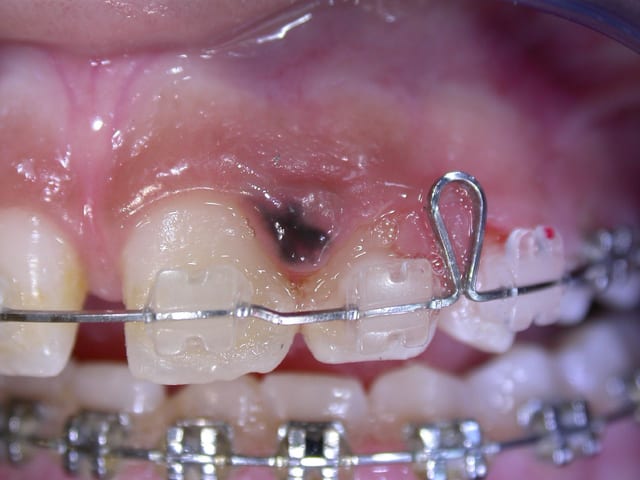

J'ai une patiente de 14 ans, martiniquaise, qui a deux taches noires sur la gencive d'apparition +- récente ( elle ne les avait pas il y a un an). J'ai un vague souvenir de coloration gingivale brune chez les patients de couleur noire, mais il me semble que c'était généralisé et pas sous forme de tache comme ici.

Je vous joins les photos...et merci d'avance pour vos lumières!!

Ds le Traité de sémio de Le Breton : pigmentation ethnique,ou endocriniene (Addison), tatouage,pigmentation medicamenteuse (plomb, anti paludeen, sels d'or), lichen nigricans (mais il devrait y avoir une lesion blanche lichenienne autour), angiome et varicosité

"Devant toute tache noire isolée... siegeant le plus souvant au palais ou sur la gencive, il faut penser à un MELANOME MALIN. ... Biopsie en milieu tres specialisé"

Bon le chirurgien étant en vacances, je n'ai pas eu le résultat extact...mais ce n'était rien, tache "ethnique"...

Résultats aujourd'hui: pigmentation lenticulaire essentielle de la gencive...rien de méchant et je suis effectivement rassurée pour ma patiente!